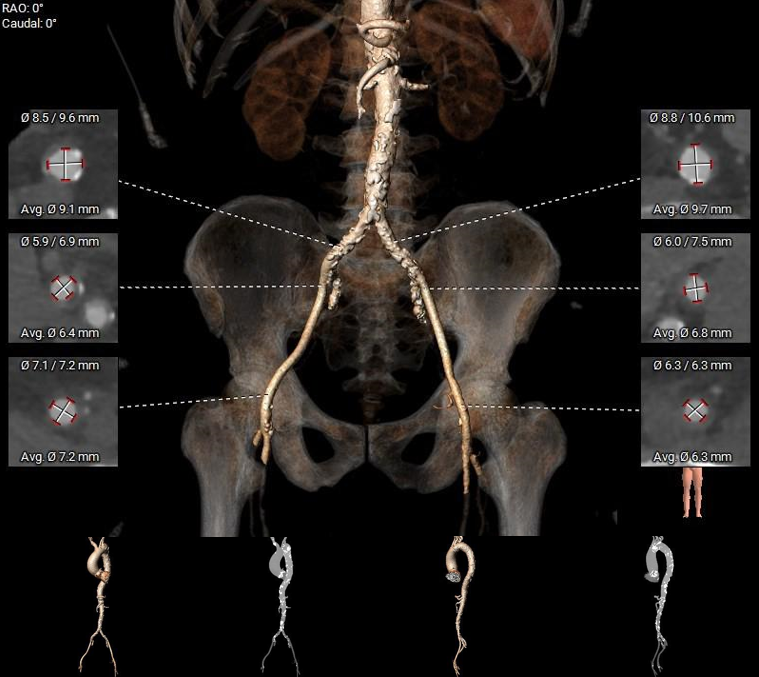

术前评估

1.主动脉瓣瓣环周长90.6mm,平均周长径28.8mm。

2.主动脉瓣成三叶式,瓣叶明显增厚伴重度钙化,钙化均匀分布与三窦瓣叶上。

3.左右冠脉开口高度可。

4. 左室腔内径较大,心室壁厚度可,横位心,升主动脉扩张。

5.双侧股动脉入路血管管径良好。

外周血管及主动脉弓解剖